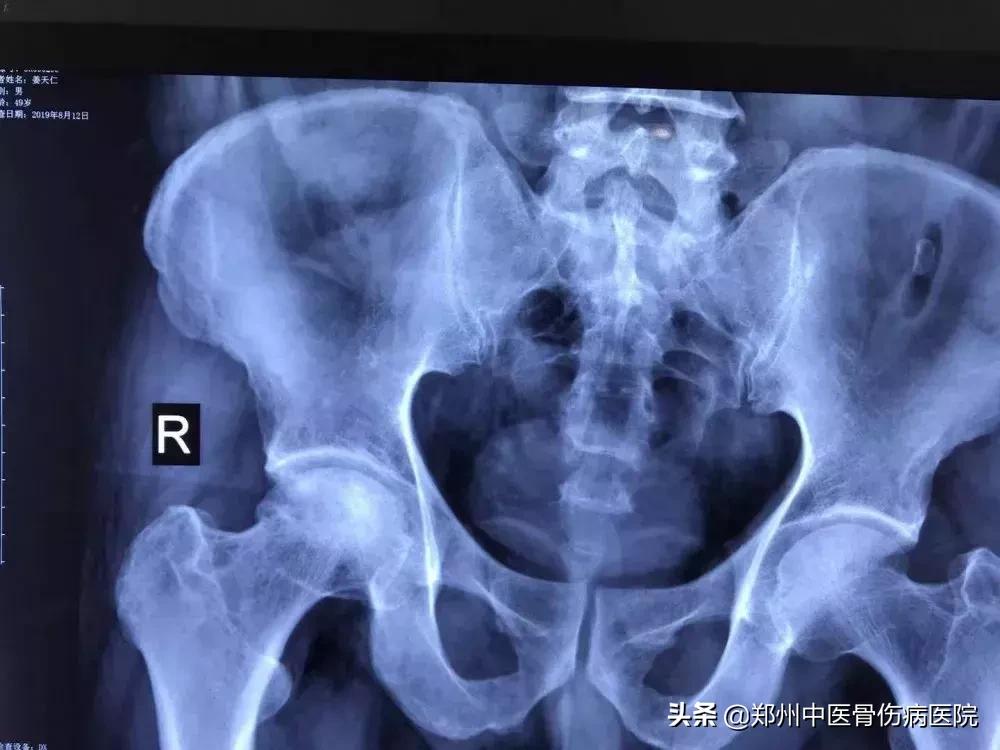

患者片子

经过龚主任一年多的跟踪指导和治疗,病人病情明显好转,于2017年3月完全康复遂停药。2018年8月病人前来复查,下蹲自如了,行走正常了,功能也恢复了,不再跛行。